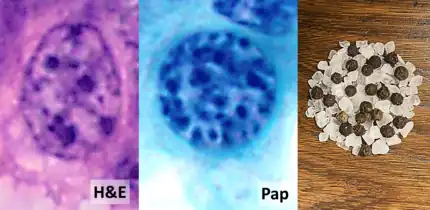

| Micrograph of a neuroendocrine tumor. H&E stain. | |